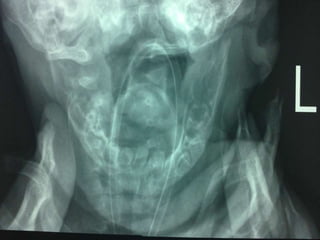

61 years old man with epigastric pain and vomiting

61 years oldman with epigastric pain and vomiting